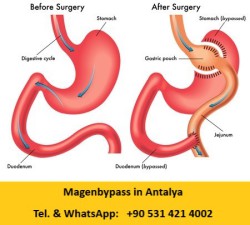

Beim Magenbypass wird der Magen wenige Zentimeter unterhalb des Mageneingangs abgetrennt. Es verbleibt ein kleiner Restmagen, „pouch", der ca. 15 ml fasst und als Bremse für die zugeführte Nahrung dient. Auch der Dünndarm wird durchtrennt. Das eine Ende des Darmes wird an den kleinen Restmagen angeschlossen und das andere so umgeleitet, dass die Nahrung und Verdauungssäfte erst im mittleren Dünndarm vermengt werden und der obere, direkt an den Magen anschließende Dünndarm umgangen („engl. Bypass") wird. Die Verdauungssäfte werden in den tieferen Darmabschnitten eingeleitet und somit kann erst hier die Verdauung durch die Aufspaltung der Nahrungsbestandteile beginnen. Die Folge ist, dass nicht alle Nahrungsbestandteile zerlegt werden können und somit nur ein Teil aufgenommen „resorbiert″ werden. Es stehen somit weniger Nahrungsbausteine dem Blut zur Verfügung. Die nicht verdaute Nahrung wird in den Dickdarm befördert.